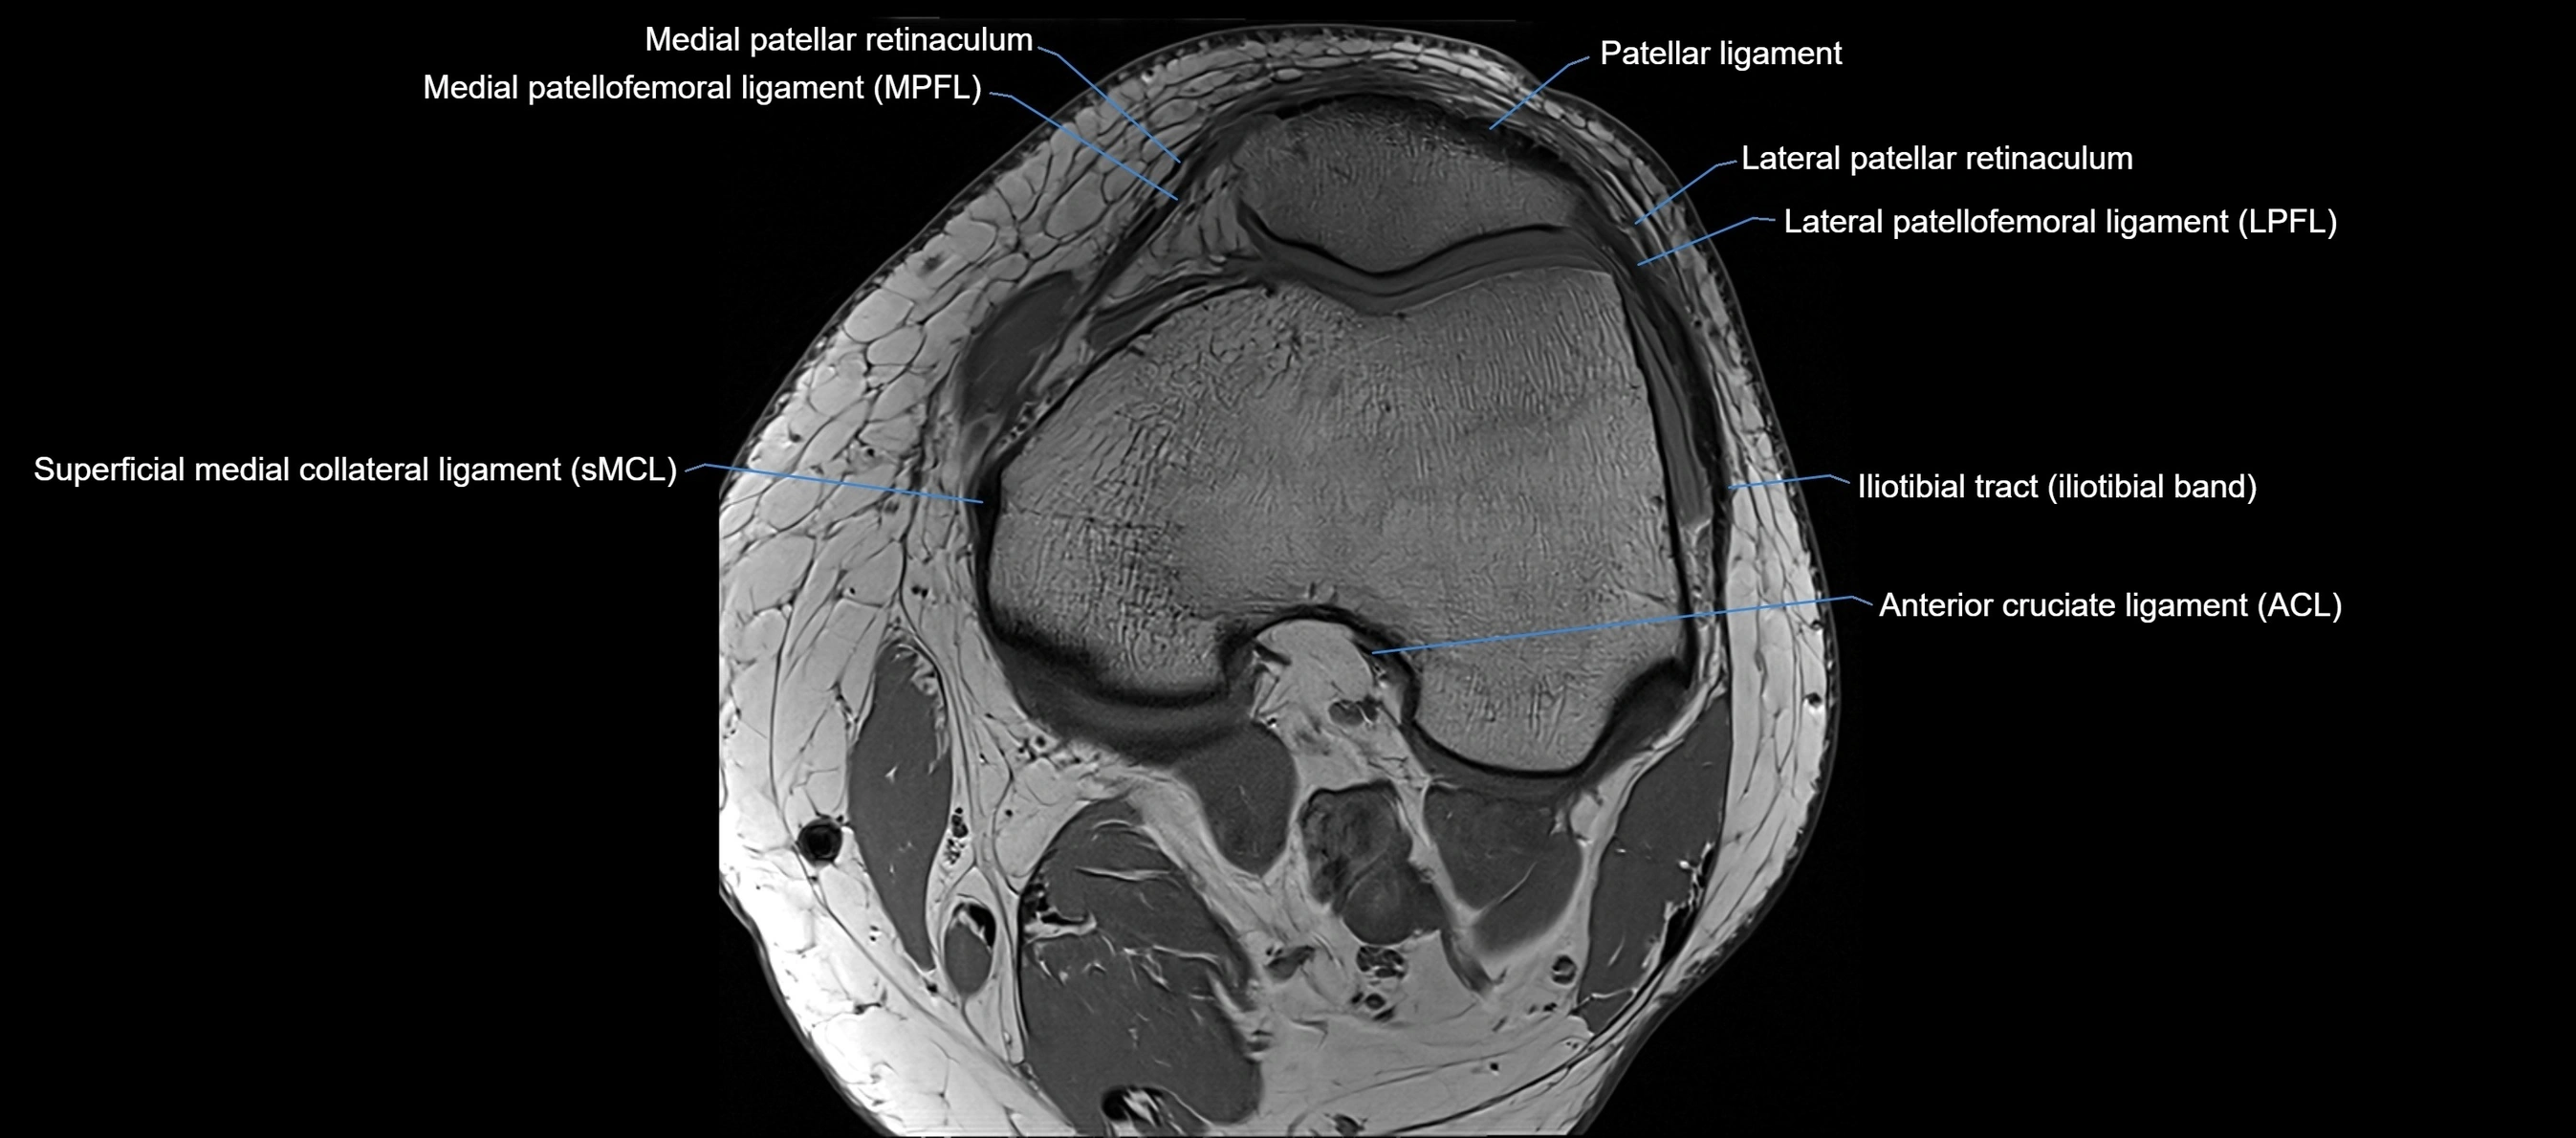

The anterior cruciate ligament (ACL) is one of the major stabilizing ligaments of the knee. It lies within the joint capsule but outside the synovial cavity. The ACL extends obliquely through the intercondylar notch, connecting the tibia to the femur, and resists anterior translation of the tibia relative to the femur. It is crucial for maintaining stability during pivoting, cutting, and deceleration movements, making it one of the most frequently injured structures in sports.

Relations

• Anteriorly: Anterior horn of the medial meniscus and infrapatellar fat pad

• Posteriorly: Posterior cruciate ligament (PCL)

• Medially: Medial femoral condyle

• Laterally: Lateral femoral condyle wall of the intercondylar notch

• Superiorly: Synovium of the suprapatellar pouch

• Inferiorly: Tibial plateau and anterior horns of menisci

MRI Appearance

T1-weighted images:

• Normal ACL appears as a low-signal band-like structure crossing the intercondylar notch

• Surrounded by intermediate signal synovial fluid and fat planes

MRI images

image